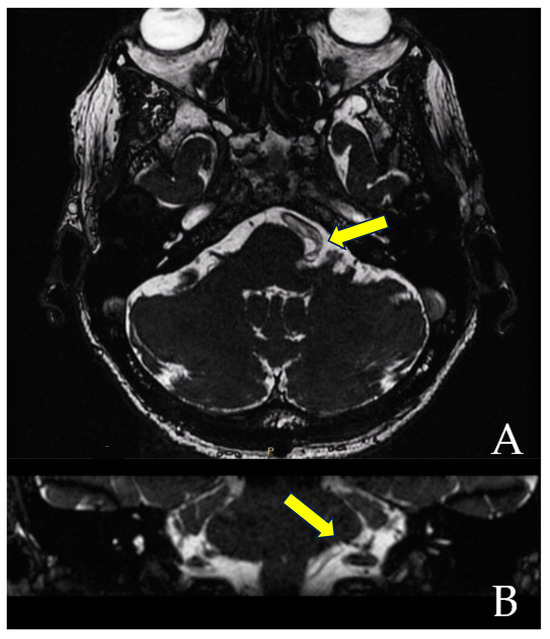

When the trajectory of the vessel is evaluated in the coronal view, it may be possible to visualize the vessel forming a loop superior and medial (towards the exit of the facial nerve) (Figure 1). When the MRI is visualized in the axial view, at the highest level of the loop in the coronal section, the proximity of the vascular structures to the pons may be seen in the axial view as if the artery was located inside of the brainstem, surrounded by the pons parenchyma (Figure 2).

The Prevedello Sign is the identification of an arterial loop enfolded by the pons near the exit of the facial nerve, in the brainstem. This finding is best visualized in T1WI with contrast and in FIESTA acquisitions of MRI sequences (Figure 3).